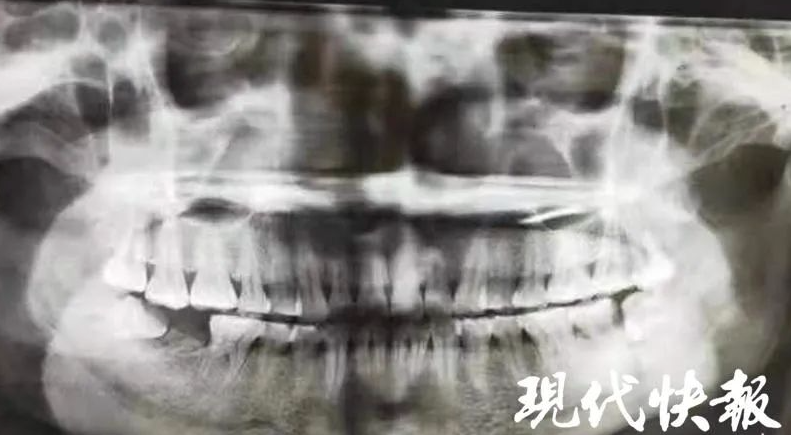

揚州大學附屬醫院口腔科主任醫生黃錦華指出,由於女子沒有及時求診,現在不僅是智慧齒,就連前面的牙齒也受波及,全都壞死了, 要全部拔掉。

黃醫生續指,女子平時不注重口腔衛生,出現智慧齒冠周炎,又長期沒有得到徹底治療,導致齒槽骨破壞缺損,臉頰被膿腫穿通。醫生表示,考慮到患者患病時間較久,導致智慧齒根尖局部炎症範圍較大,因為智慧齒牙根距離下牙槽神經管較近,第二磨牙也已經完全壞死,於是決定分兩步對患者進行治療,首先對患者局部炎症進行有效控制,然後為其施行智齒拔除、第二磨牙拔除。